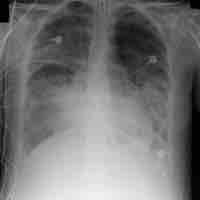

Respiratory Diseases and Disorders

Thumbnail

Asthma

Asthma is a common chronic inflammatory disease of the airways characterized by reversible airflow obstruction and bronchospasm.

Respiratory Distress Syndrome

Acute respiratory distress syndrome (ARDS) is a serious reaction to various forms of injuries or acute infection to the lung.

Cystic Fibrosis

Cystic fibrosis (CF) is an autosomal recessive disorder leading to respiratory congestion, multiple organ failure, and metabolic changes.

Hypoxia

Hypoxia, or hypoxiation, is inadequate oxygen supply to the body as a whole (generalized hypoxia) or a region of the body (tissue hypoxia).